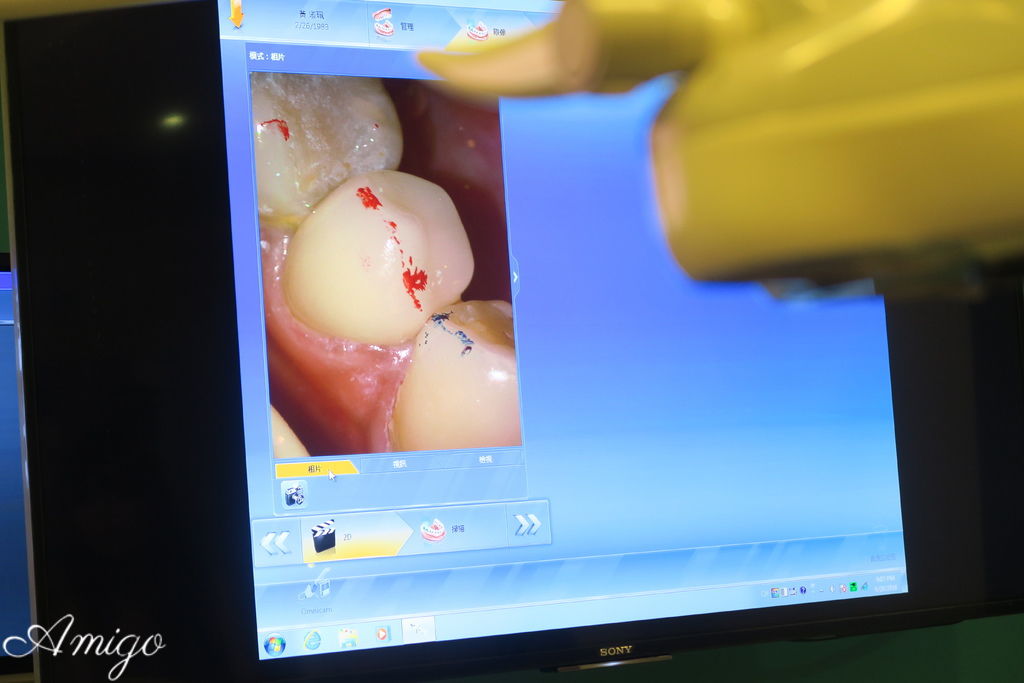

明亮的診間裡

透過大螢幕來觀看患者口內狀況以及3D影象投射

整個治療過程都在螢幕上清楚呈現

當天的case是一位做全瓷冠假牙的患者

本次病患做假牙的部位是畫面左邊倒數第三顆的小臼齒

將口內牙齒狀況以3D彩色影像精準呈現在技師的工作螢幕上

技師在診間內即可使用全瓷假牙設計軟體預視患者的牙齒

透過取像儀檢視

邊緣的密合度高 加上逼真的全瓷牙冠

幾乎分不出來哪一顆是假牙